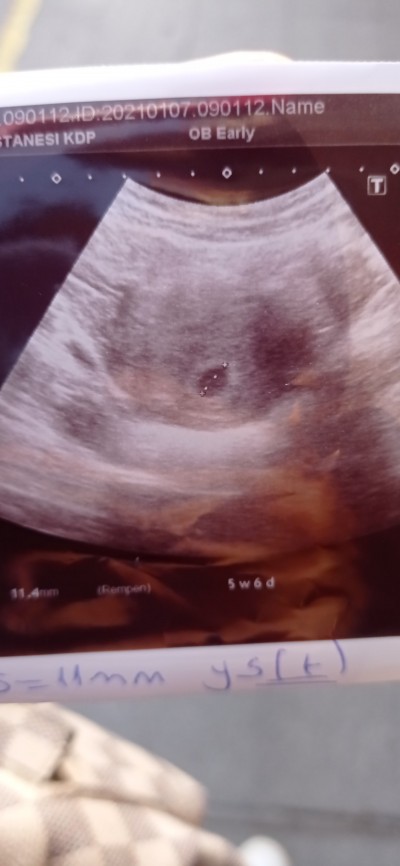

5 Haftalık Hamileyim Kese Var Bebek Yok.